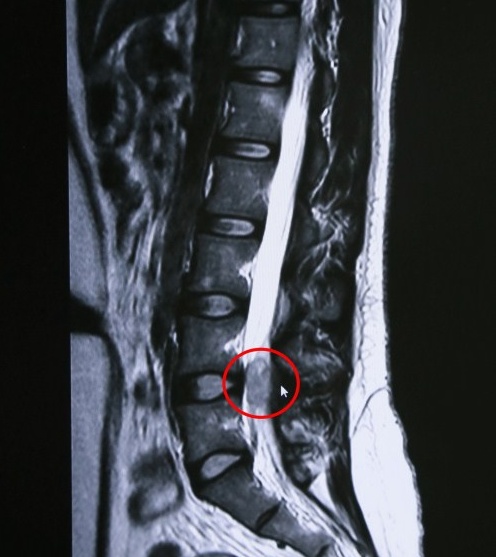

顧大叔長脊膜瘤的部位

家住虹口區(qū)的顧大叔,腰腿經(jīng)常麻木、疼痛,特別晚上睡覺時(shí)疼痛得輾轉(zhuǎn)難眠,去過多家大醫(yī)院檢查治療,看過骨科、心內(nèi)科甚至泌尿科,病情沒有緩解反而加重,后來到藍(lán)十字經(jīng)核磁共振檢查,孫海輝主任發(fā)現(xiàn)顧大叔L4/5椎間盤水平椎管點(diǎn)位,原來是脊髓內(nèi)長了一個(gè)腫瘤!經(jīng)過手術(shù)后,顧大叔康復(fù)出院。